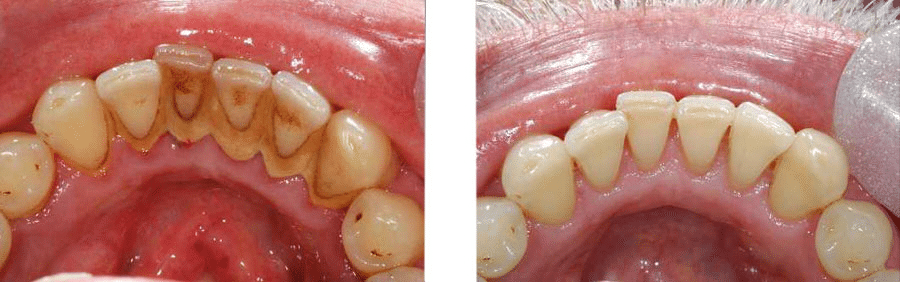

Za početak, pogledali ste se u ogledalo i primjetli ružnu boju donjih zuba, a ni gornji nisu kao nekada. S unutrašnje strane donjih zuba sve je nekako tamno. No, ne brinite, jer to može biti zubni kamenac kojeg se možete riješiti jednim posjetom stomatološkoj ordinaciji. Eto vam razlog za odlazak zubaru. Mi vam to riješimo s ultrazvučnim skidačem, bezbolno, u jednoj posjeti. Uvijek kažem pacijentima: “Sada smo skinuli okove s vaših zubi i sada će oni kući pjevajući!” Ni ne znate koliko ste učinili za zdravlje svojih zubi s tim što ste očistili kamenac. To nije ništa strašno, a vi i vaši zubi ćete biti veseli! Zubi – zato jer smo uklonili mehaničke zapreke čišćenju zubi, sve bakterije koje žive na tom kamencu i uzrokuju upalu parodonta, a vi – jer se osjećate čisto i zdravo.

Ono što niste dobro oprali danas zove se plak, a već sutra se kalcifikacijom pretvara u kamenac. I tako u krug, svakim danom stiže novi sloj koji vi sami ne možete skinuti, već samo vaš zubar.

Nakon što smo očistili kamenac, zube treba dobro zglancati da se ulovi što manje novog kamenca.

To ćemo učiniti pjeskarenjem, koje daje potpunu čistoću i visoki sjaj.